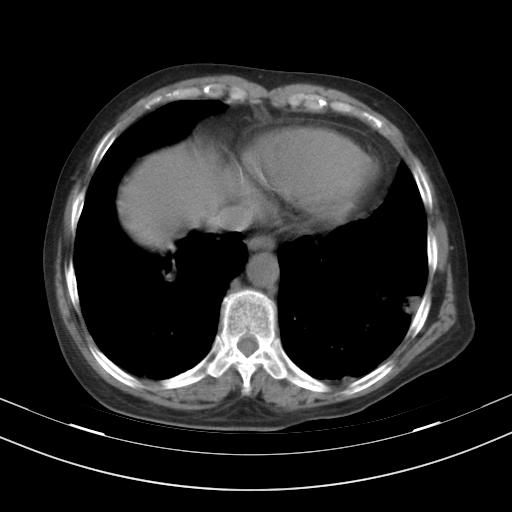

老年女性,嗜睡3天,意识模糊。轻咳,无发热。

1)两肺感染性病变;建议抗炎治疗后复查。2)纵隔淋巴结肿大。3)左侧胸腔积液。

1)先考虑两肺感染性病变;建议抗炎治疗后复查。

2)纵隔淋巴结肿大。

3)左侧胸腔积液。